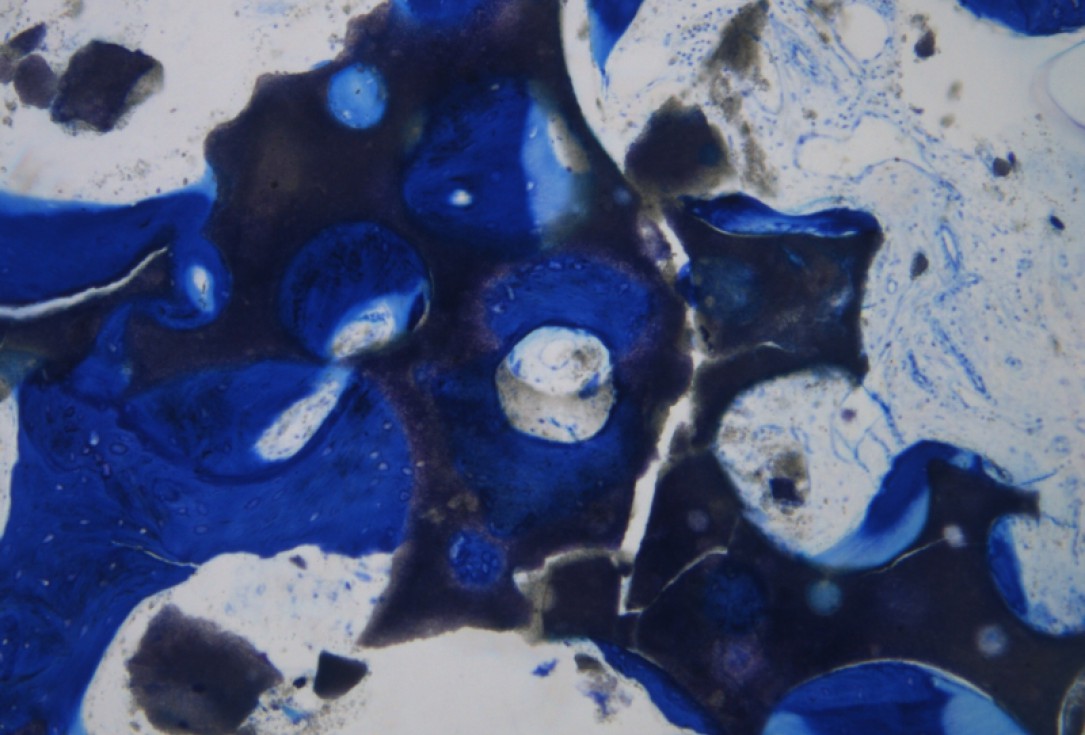

14/20 - Histology showing maxresorb® particles integrated in newly formed bone matrixGBR with maxresorb® & Jason® membrane - Prof. Dr. Dr. D. Rothamel

18/20 - Histology showing the integration of maxresorb®GBR with maxresorb® & Jason® membrane - Prof. Dr. Dr. D. Rothamel